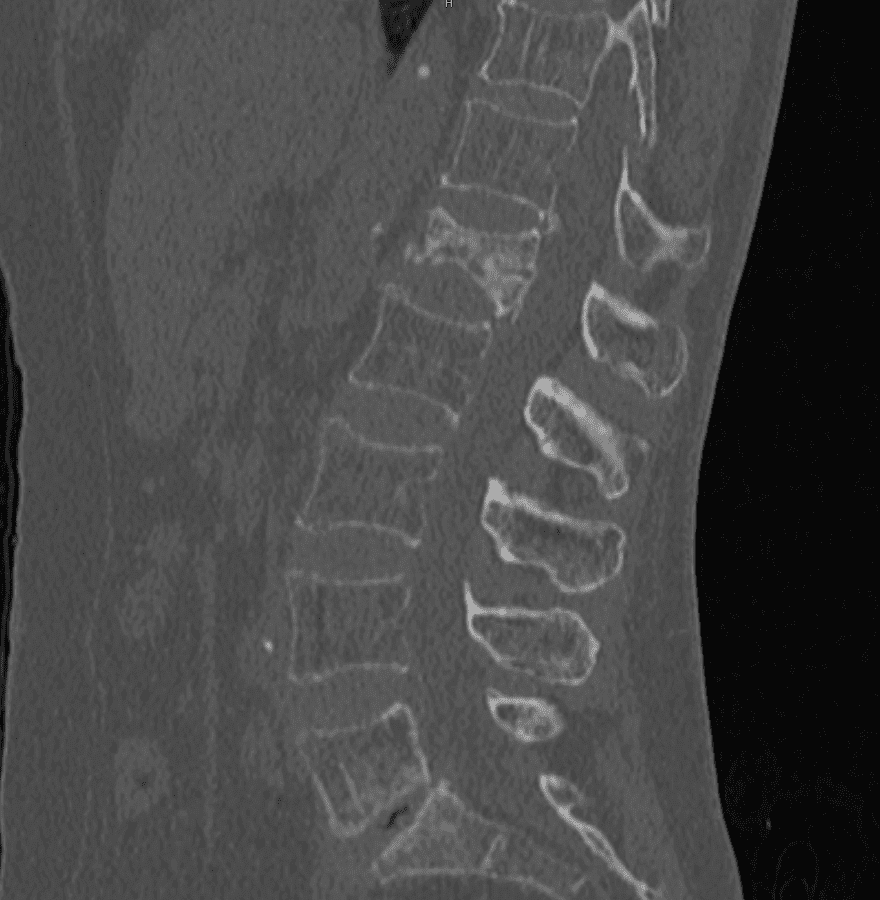

Scanner

Scanner montrant une fracture d'une vertèbre